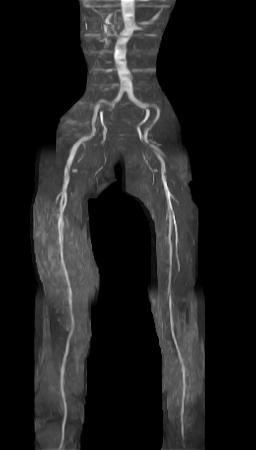

| MRIとは(Magnetic Resonance Imaging:磁気共鳴画像)の略称です。MRI検査は強力な磁力と電波を用いてからだの臓器や血管を映しだす検査です。レントゲンやCTなどのX線を使用した検査ではありませんので被ばくの心配がありません。

当院では日立メディコ社製 1.5テスラMRIを導入しており、比較的短い時間で信頼性のある検査が可能となりました。 |